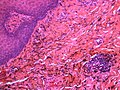

Microscopic

Features:[20]

- Fine powdery black material in the subepithelial tissue - key feature.

- May be clumped.

- Found between collagen fibres.

- +/-Foreign body-type giant cells - uncommon.